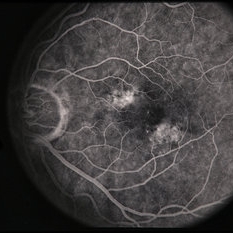

---thumb.jpg/image-square;max$300,300.ImageHandler) Age Related Macular Degeneration - Geographic Atrophy

Age Related Macular Degeneration - Geographic Atrophy

May 3 2013 by Suber S. Huang, MD, MBA, FASRS

Geographic Atrophy.

Imaging device: Retina Diseases Imaging Analysis Reading Center

Condition/keywords: advanced geographic atrophy, atrophic scar, atrophic spot, geographic atrophy, macula lesion, pigment epithelial atrophy